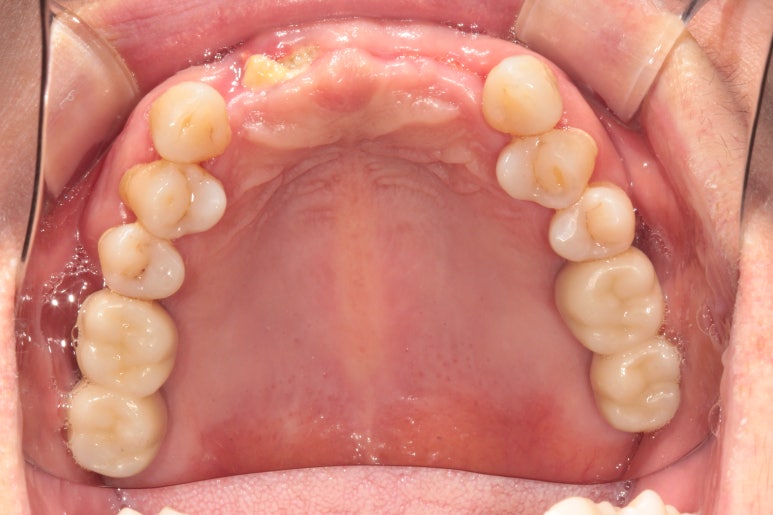

3달이 지나.. 드디어 임플란트 2차수술을 하였습니다.

그리고 다음주에 드디어 뽄뜨는 시간 !! (인상채득)

임플란트 2차수술을 하게 되면, 왼쪽에 보이는 것처럼 동그란 뚜껑이 튀어나오게 됩니다.

이 상태로 1-2주 정도 기다리면 잇몸이 깨끗하게 아물죠! 그러면 비로소 치아를 만들기 위해 뽄을 채득합니다.